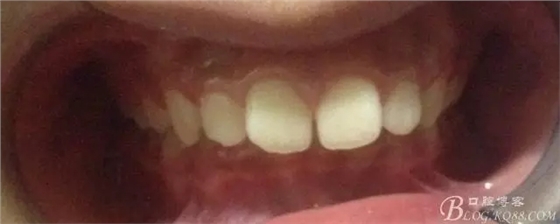

術(shù)前側(cè)貌,下合后縮還算明顯,正面照有點(diǎn)看不出的樣子!